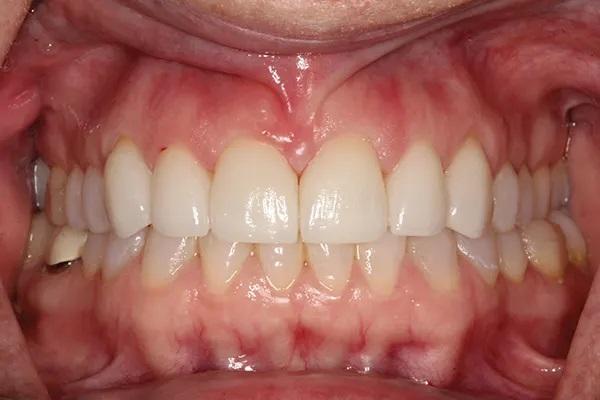

Для постоянной фиксации виниров использовался полупрозрачный цемент (RelyX Veneer Cement, 3M Oral Care) виниры были зафиксированы парами начиная с области центральных резцов, затем латеральные резцы и заканчивая клыками. Каждую реставрацию закрепляли с помощью 3-секундного светового отверждения, а излишки цемента удаляли с помощью ультразвукового скеллера. Окончательное отверждение осуществлялось путем полимерезации светом в течение дополнительных 20 секунд на каждый зуб. Результаты проведённого лечения показаны на фото с 9 по 12. Изменение улыбки пациентки с фиксированными постоянными реставрациями (фото 9). Демонстрация смыкания после лечения (фото 10). Портретная фотография анфас с широкой улыбкой (фото 11). Прицельные снимки зубов пациентки после проведенного лечения (фото 12).

Фото 9